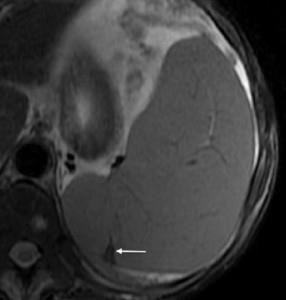

Infarktus a lép be a képen

Adenoma (nyíl) a jobb mellékvese. Adenoma formájában van egy kis hypodenz formáció homogén szerkezetű képen